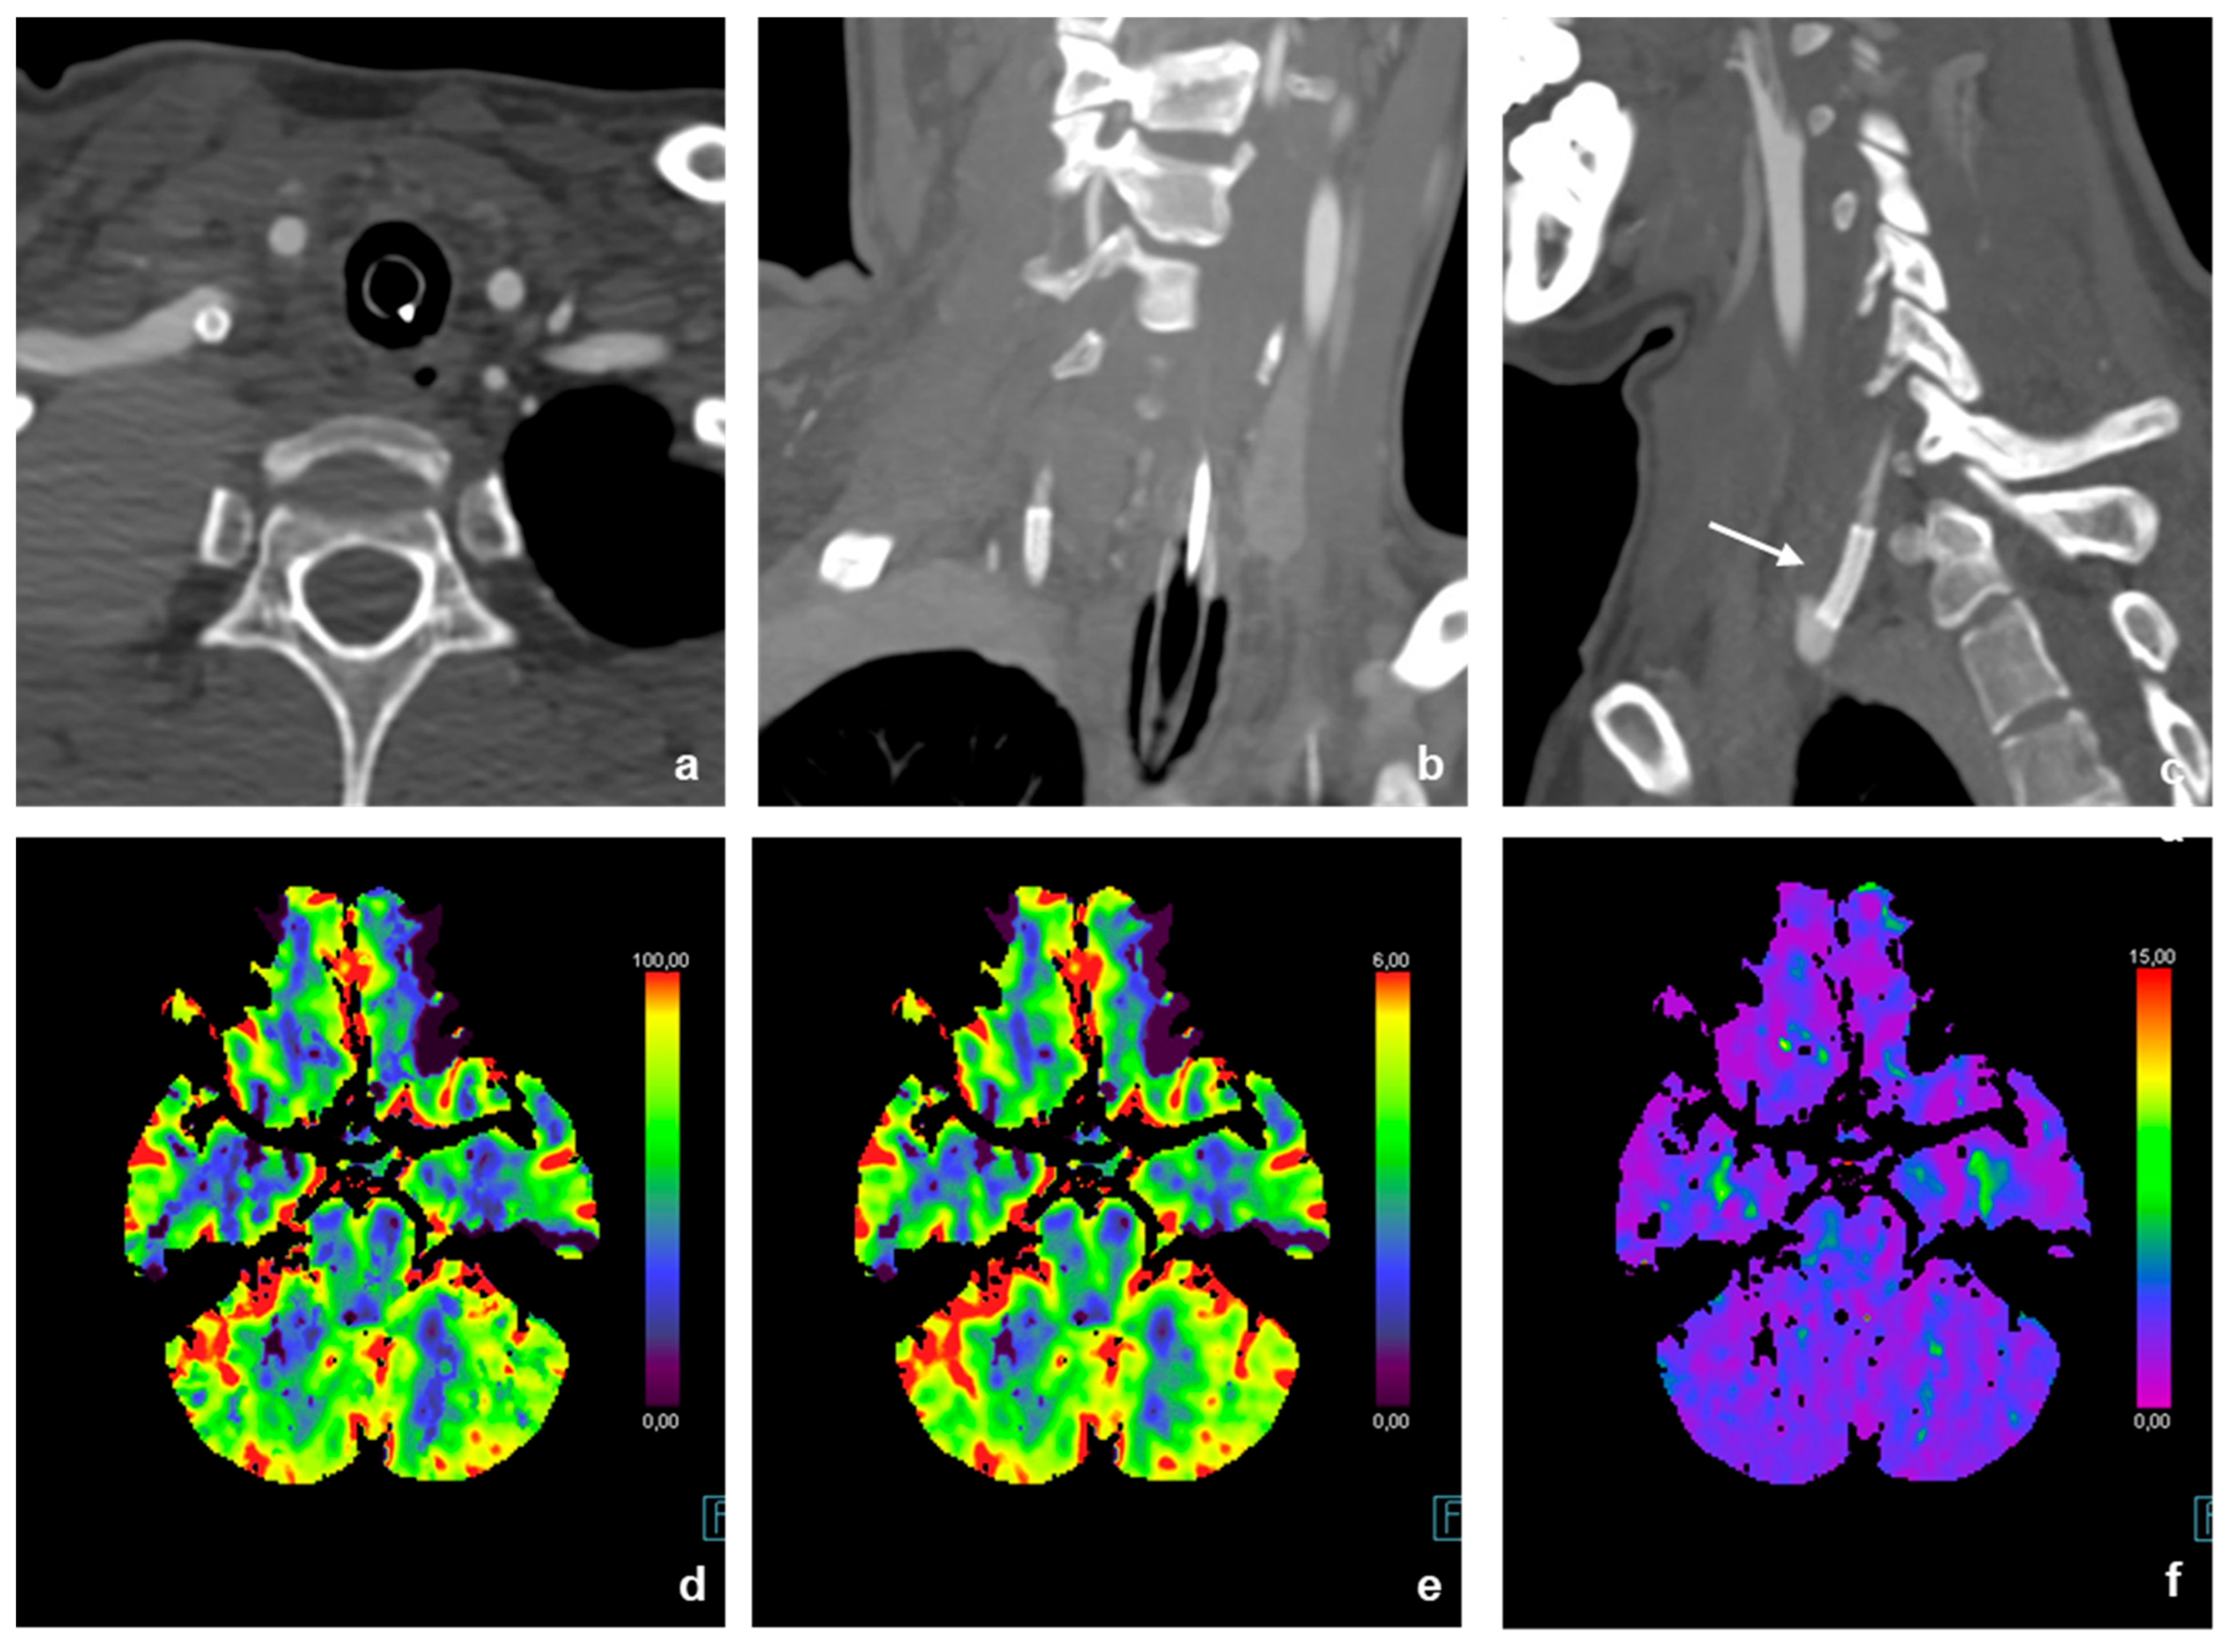

3.1. Image Acquisition

3.2. Neurointerventional Procedure

3.4. Postinterventional Result